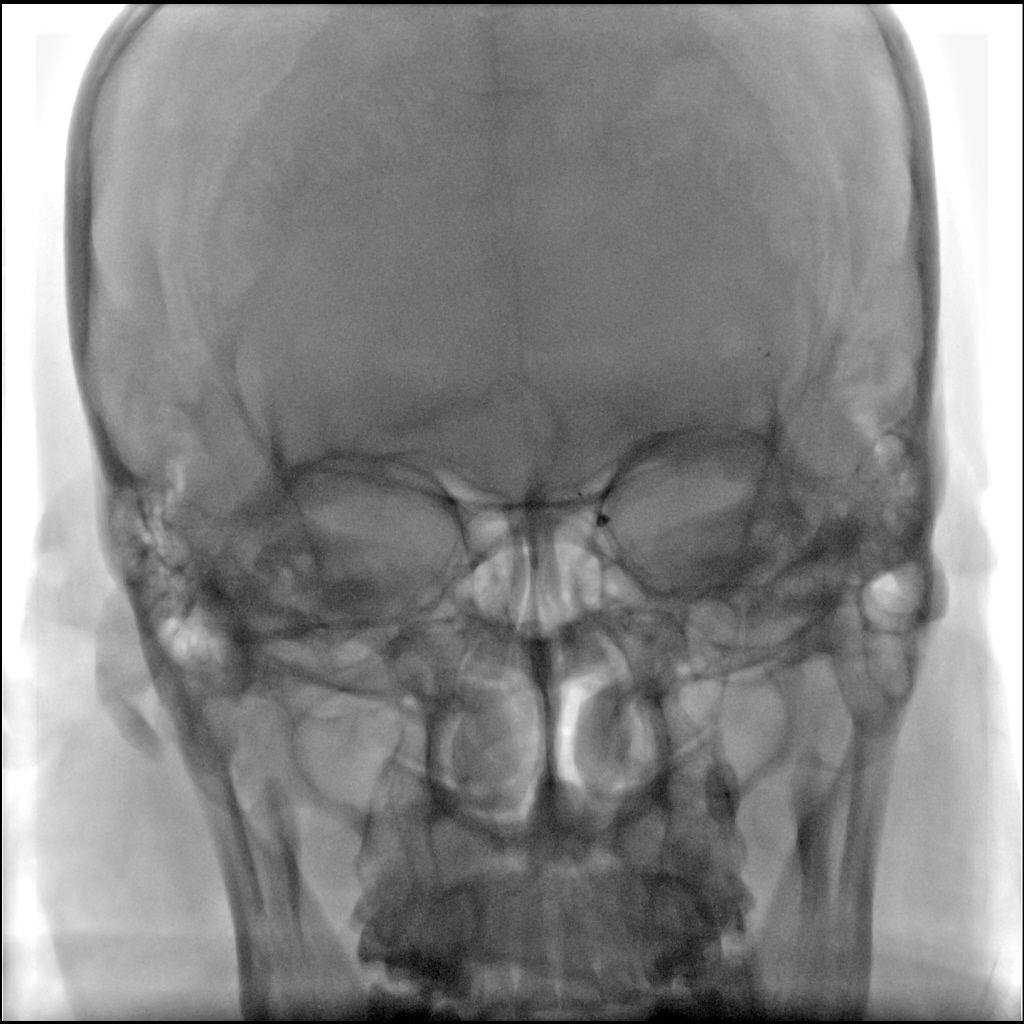

术前影像

图1急诊颅脑CT

图2 CTA显示左侧大脑中动脉M1段闭塞